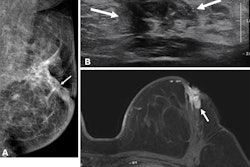

Use of preoperative MRI to manage newly diagnosed breast cancer has increased over the past 20 years, but as its moderate specificity can lead to false positives, debate over which patients should undergo the exam continues, the team wrote. Significant evidence exists that women in racial and ethnic minorities and those from lower socioeconomic backgrounds often face barriers to breast cancer screening as well as advanced imaging for further diagnostic workup, but "little research has focused on potential racial and socioeconomic disparities in the use of preoperative MRI among patients with newly diagnosed breast cancer," the group explained.

- The rate of preoperative breast MRI increased with increasing breast density (p < 0.001) and higher tumor stage (p < 0.001).

- The rate of preoperative breast MRI was also influenced by receptor status and histology, with the highest use in patients with HER2+ enriched disease (p < 0.001) and patients with invasive lobular carcinoma (p < 0.001).

- Among those who received preoperative breast MRI, 51.5% were found to have additional suspicious lesions, and 69.1% of these patients underwent an image-guided biopsy.

- Patients who had a preoperative breast MRI exam underwent mastectomy more often than those who did not (49% compared with 31%, p < 0.001) but were less likely to require reexcision (8% compared with 14%, p < 0.001).